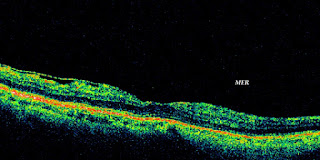

RETINOGRAFIAS XI

Dada la importancia del hecho, seguimos con sesiones de degeneracion macular seca incipientes y moderadas.

La OCT nos facilita su seguimiento , para ver estas drusas en profundidad, y si acontecen con liquido o quistes.

OCT MACULA IV

Con el paso de los años, descubrimos cuanto ha hecho la tomografia láser por el buen diagnóstico en retina; en concreto para la mácula.

Os adjuntamos las ultimas OCT